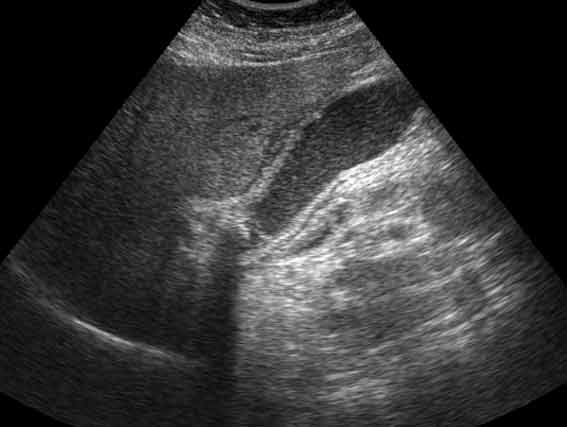

УЗИ: ЖКБ, острый обструктивный холецистит

ЖКБ, острый обструктивный холецистит. В шейке желчного пузыря - вклиненный конкремент. Стенки равномерно утолщены и слоисты.